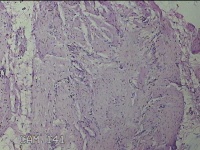

子宫体肌瘤结节

性别

女

年龄

32岁

临床诊断

子宫肌瘤 疤痕子宫

一般病史

发现子宫肌瘤数月余。

标本名称

大体所见

灰白色圆柱形条索状组织10x7.5x1.8㎝一堆,切面均为灰白色结节状或编织状,质中。